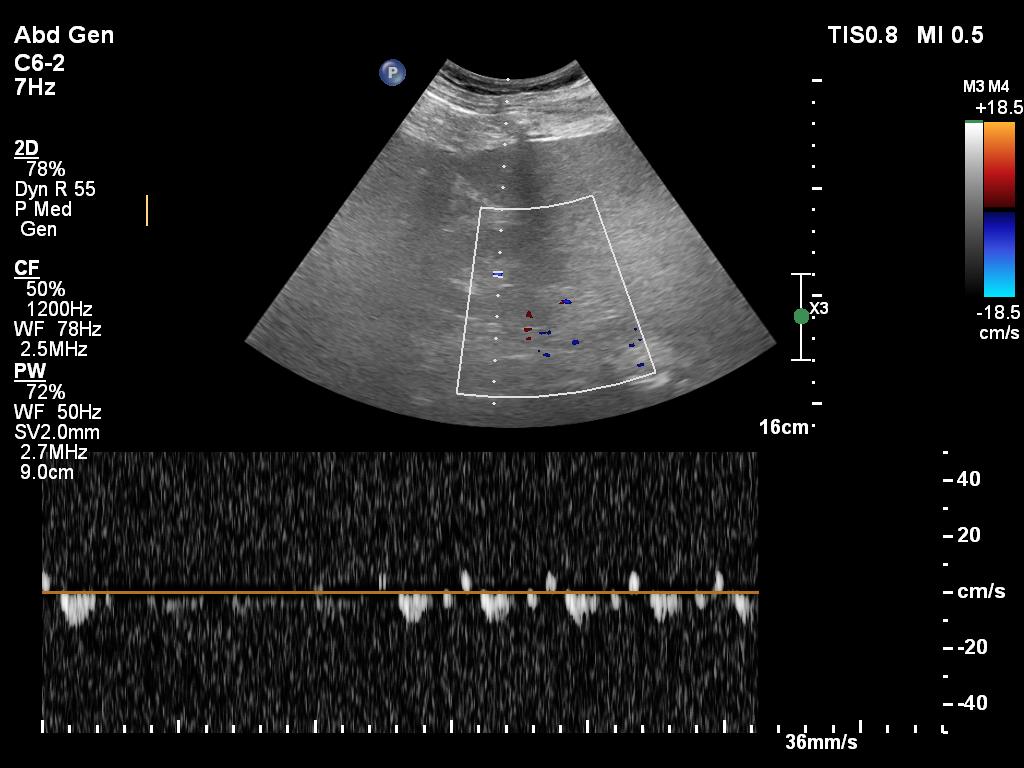

8/ and VEXUS...although not easy and quality not ideal

hepatic vein

9/ portal vein

10/ renal vein (or not :)

20/ My interpretation of VEXUS is Grade I: normal hepatic vein, mild portal vein pulsatility and biphasic renal vein flow. But pancreatitis is a 'leaky' state, so VEXUS is often not very abnormal as fluid readily leaks to the tissues.